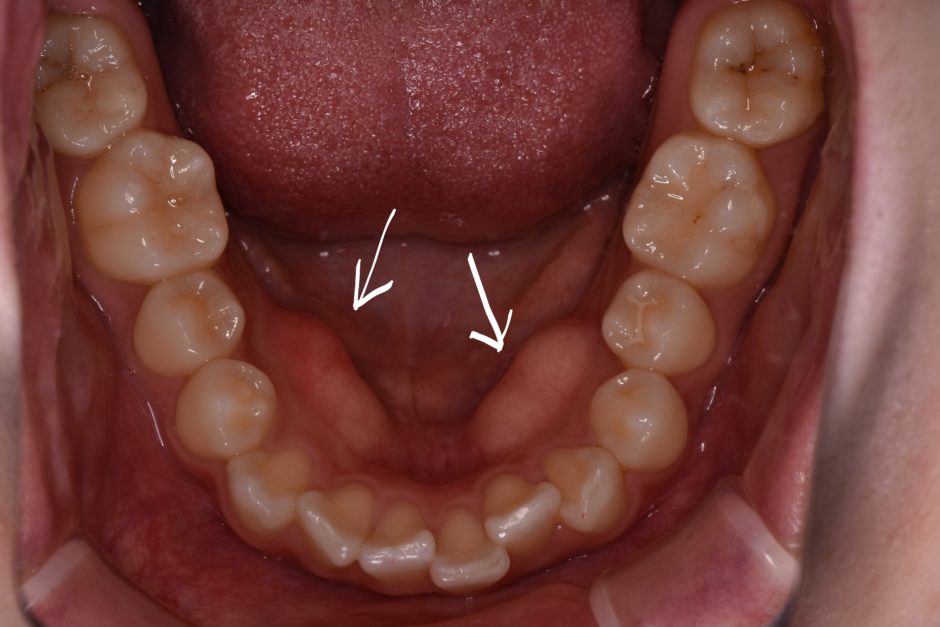

お口の中を観察してみて下さい。 歯の裏側(舌側)や上顎中央部にぼこっとした凹凸のようなものはありますか?

この凹凸のようなものを骨隆起と言います。漢字の通り骨が発達して盛り上がっているもののことです。

別名、外骨症(がいこつしょう)、外発性骨増生(がこはつせいこつぞうせい)とも言われ、上あごにできる骨隆起を「口蓋隆起(こうがいりゅうき)」、下あごにできるものを「下顎隆起(かがくりゅうき)」といいます。

骨隆起自体に、あまり自覚症状はありませんので、歯科を受診した際に、指摘を受けて骨隆起の存在を知ることが多いようです。 指摘後に初めて指や舌で触ってみると、どことなく骨の凸凹に違和感を覚え始めるみたいです。